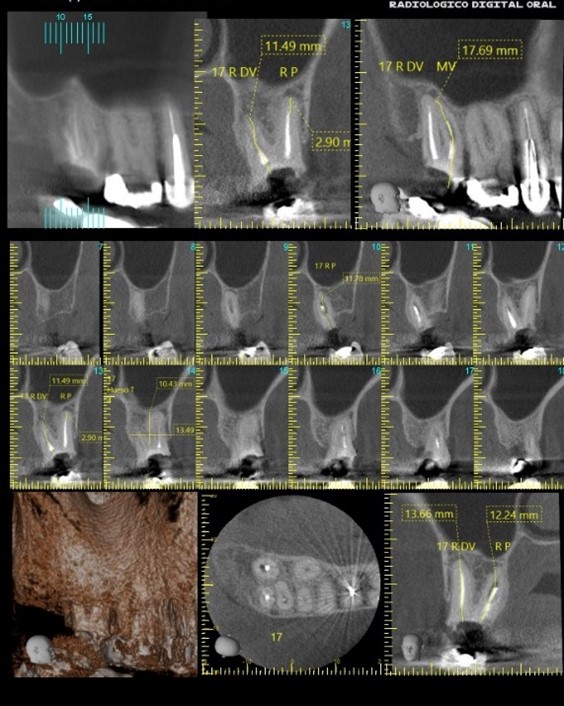

Se toman radiografías periapicales y/o imágenes radiológicas más avanzadas, como tomografías computarizadas dentales, para evaluar la anatomía del conducto radicular y detectar la presencia de infecciones, fracturas o complicaciones relacionadas con el tratamiento previo.

En este caso, el odontólogo especialista ve como mejor opción realizar tomografía en zona del diente 17 y al realizar el debido estudio se puede observar imagen peri apical normal, tratamiento endodóntico inadecuado, conductos obturados con fallas en condensación vertical y lateral de mayor predominio en raíz Palatina. Riesgo de con foco infeccioso por infección apical, sin alteración de la continuidad en la cortical.